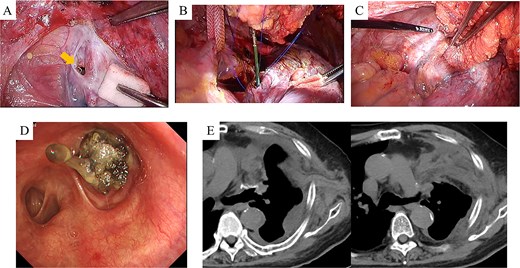

At 1 month postoperatively, CT imaging revealed a small air space adjacent to the upper lobe bronchial stump (Fig. 1A). In the absence of infection, conservative observation was chosen. Despite the patient remaining asymptomatic, subsequent CT scans at 3 and 6 months demonstrated gradual enlargement of the air space (Fig. 1B and C). Bronchoscopic evaluation showed failure of the staple line at the upper division bronchus (B1 + 2, B3) near the bronchial stump, resulting in a complete separation of ~10 mm with surrounding whitish changes (Fig. 1D and E). An infection-free upper lobe BPF was diagnosed, and a one-stage closure using a latissimus dorsi flap was planned.

CT and bronchoscopic findings post-left upper lobectomy (LUL). (A–C) CT scans obtained at 1, 3, and 6 months postoperatively. Panel A shows a small airspace (gold arrow) near the upper segment of the bronchial stump that progressively enlarges over time. (D–E) Bronchoscopic images at 6 months demonstrate failure of the staple line for the upper division bronchus (B1 + 2, B3) at the upper lobe bronchial stump, resulting in an ~10 mm complete separation with surrounding whitish changes.